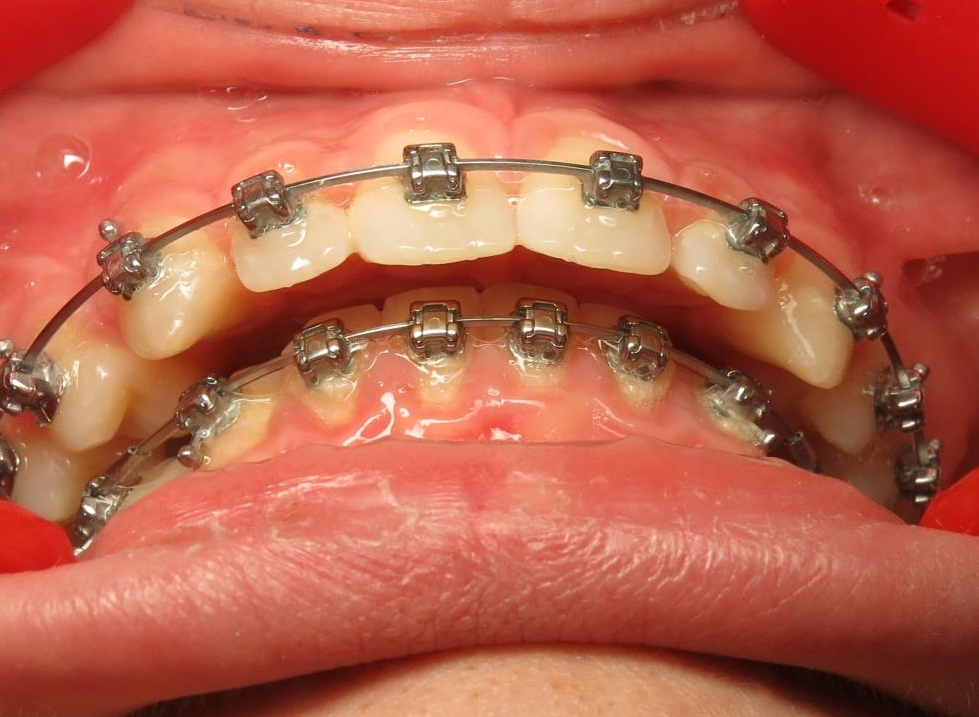

2 - Préparation orthodontique et résultat après chirurgie

Les photos supérieures montrent les arcades juste avant la chirurgie, avec un alignement complet et des axes dentaires physiologiques. La largeur de l’arcade maxillaire a été préparée pour permettre un emboîtement optimal après l’avancée mandibulaire. En bas, les photos post-opératoires montrent des arcades désormais coordonnées, avec une occlusion stable et harmonieuse, grâce à une préparation rigoureuse en amont de l’intervention chirurgicale.